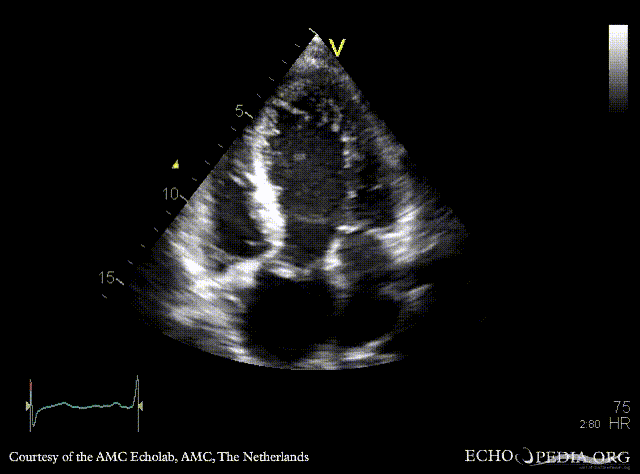

PLAX: dilated left ventricle and ascending aorta in patient with Marfan syndrome PLAX: dilated ascending aorta